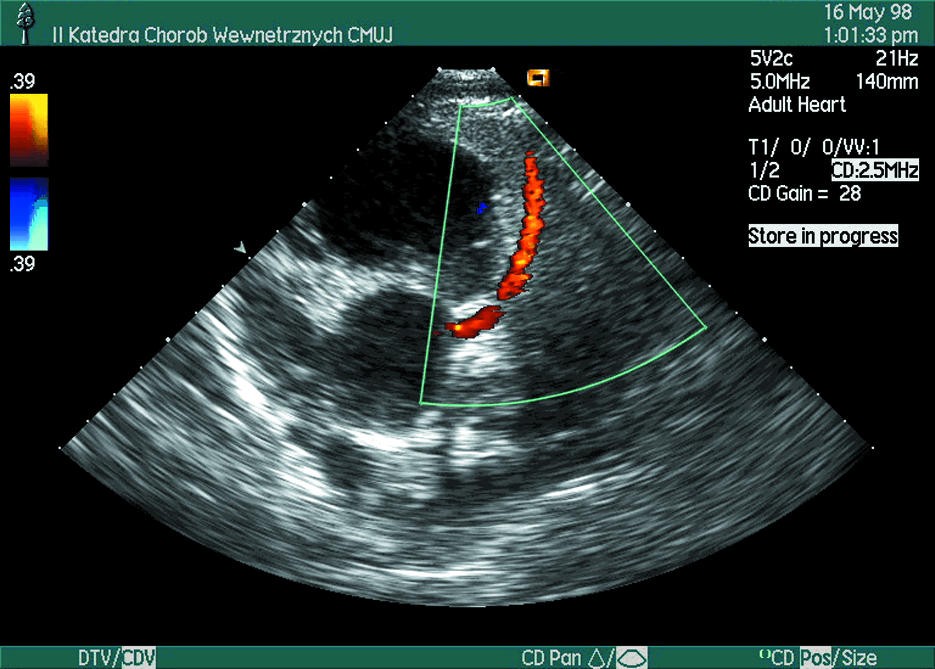

Ecografía Doppler en circulación coronaria

En cardiología moderna, no basta con conocer la anatomía coronaria. En muchos escenarios clínicos, la pregunta clave no es solo si existe una estenosis, sino cómo está afectando el flujo.

Aquí es donde la ecografía Doppler en circulación coronaria adquiere relevancia. El ultrasonido, a través del Doppler integrado en el ecógrafo, permite evaluar patrones de flujo y estimar repercusión hemodinámica.

Aunque la visualización directa de arterias coronarias epicárdicas es limitada por vía transtorácica, el Doppler aporta información funcional complementaria en contextos específicos.

La ecografía Doppler en circulación coronaria es una modalidad de ultrasonido que permite evaluar el flujo sanguíneo mediante cambios en frecuencia reflejada por las células sanguíneas en movimiento.